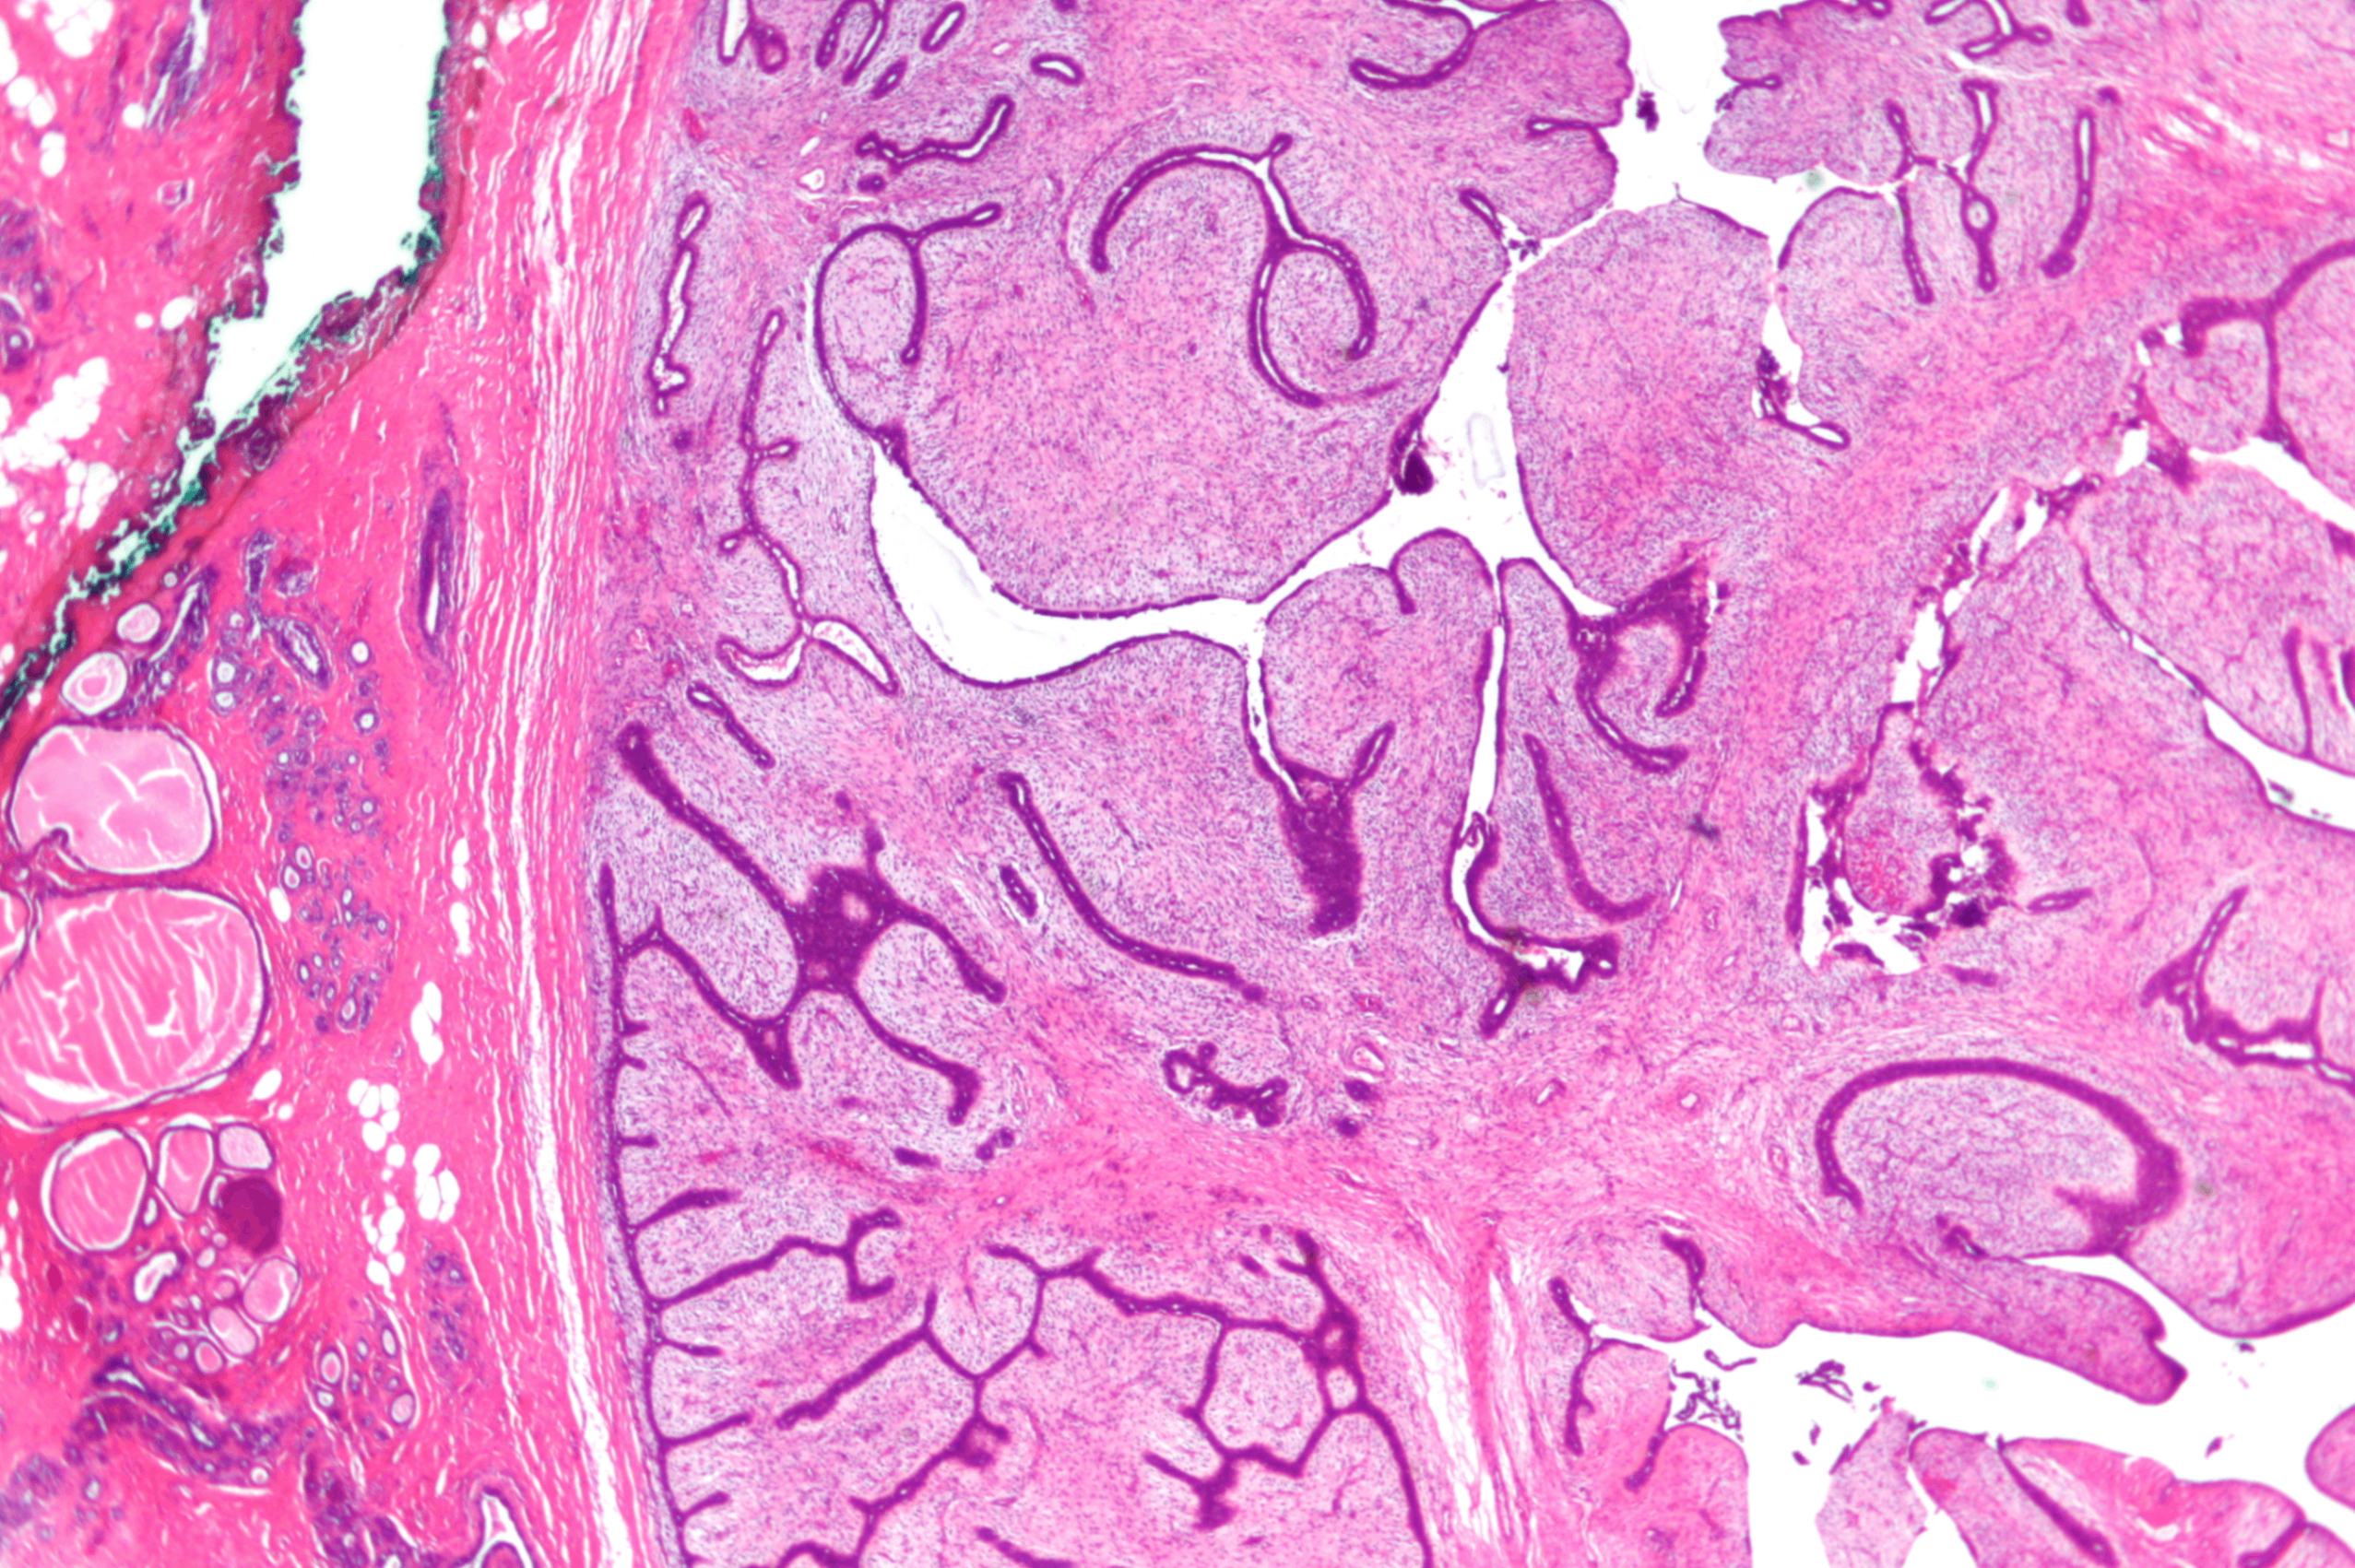

(3) 관내유두종 (intraductal papilloma)

• 유관 내에 발생하는 양성 상피-섬유성 병변

유두 분비물, 특히 혈성 분비물이 흔히 관찰됨

Fibrovascular core을 중심으로 luminal epithelial cell과 myoepitheli cell이 유두 모양으로 증식해 유관 내강을 채움

Intradcutal papilloma, Wikipedia Commons